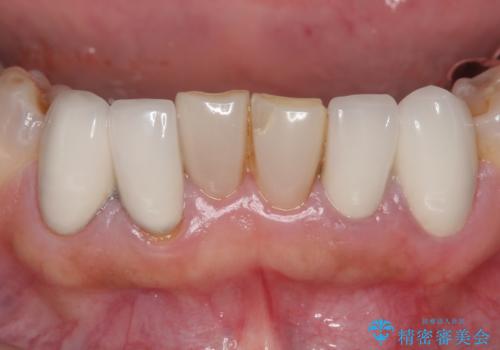

下顎は左側 4 番目から右側 4 番目までの 8 歯と左下 567 ブリッジをオールセラミッククラウンで補綴し、右下67の銀歯はセラミックインレーによる修復を行いました。

セラミックインレーについて

当院のセラミックインレーはemaxという強度と審美性に優れた材料を使用しています。

またプレス方式でインレーを製作しているため、削り出しで製作するCADCAMより優れた適合性も持ち合わせており、虫歯が再発しにくい修復物です。